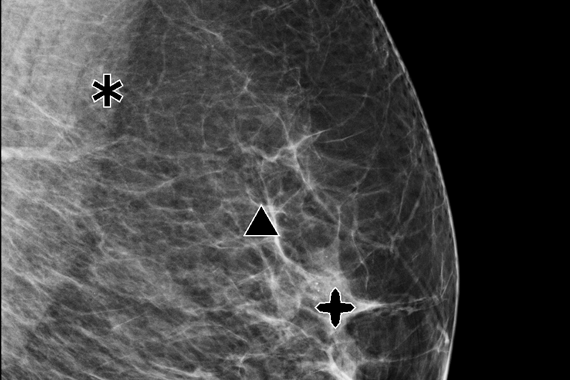

Genius AI™ Detection

Using deep learning technology, Genius AI Detection software finds cancers with better accuracy than Hologic’s previous generation CAD10-11, with the software fully integrated on the Dimensions® AWS. Genius AI Detection technology identifies areas of interest on all Hologic Dimensions image types – now and into the future.

Identifies potential cancers in breast tomosynthesis images with high accuracy. Use of Genius AI™ Detection software resulted in a difference of +9% in observed reader sensitivity for cancer cases. CAD10